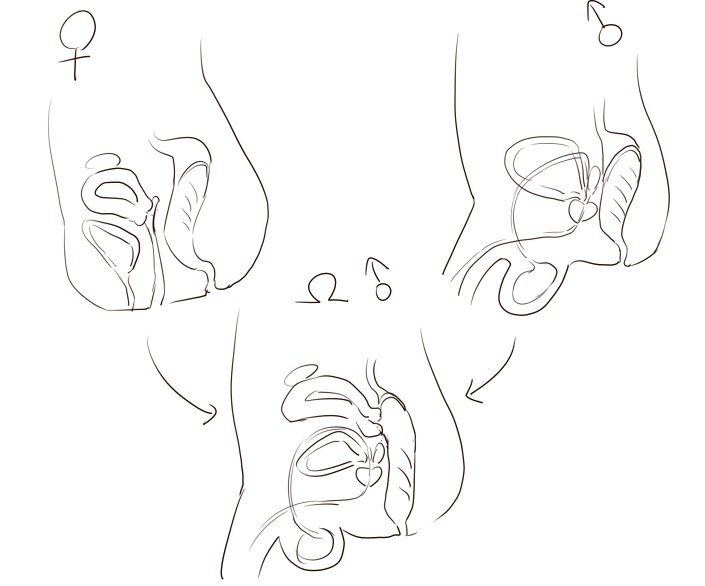

まつえー 夢見る体育座り Twitterren 男女の断面図を比べるとこうなるんですが 実際 子宮口と直腸って距離的にはほとんど離れてないわけで 組み合わるとこうなる おお

マジメに解説するメスイキの仕組み オトコの解剖生理学 学校では教えてくれない 性 のこと セクマイセラピストの保健授業